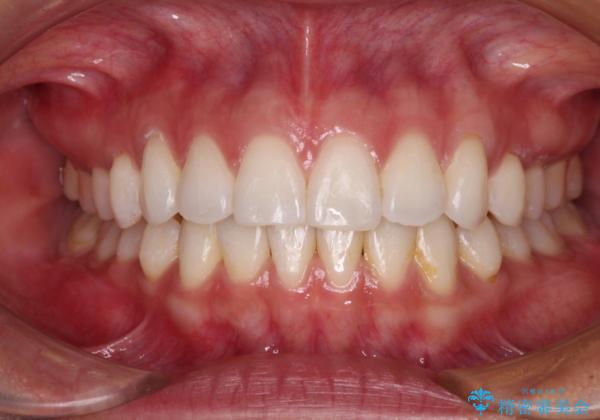

【モニター】インビザラインで口を閉じやすく

- 前に出ている上顎前歯が気になるとのことで来院された患者様です。

インビザラインを用い、IPR(歯と歯の間を削る)と歯列全体を後方に移動させることで、可能な限り前歯の突出感を改善することとしました。

元々の歯列も整っており、横顔の印象の出っ歯ではなかったため、仕上がりに満足できない可能性があると心配しておりましたが、口が閉じやすくなり、患者様には大変満足していただきました。